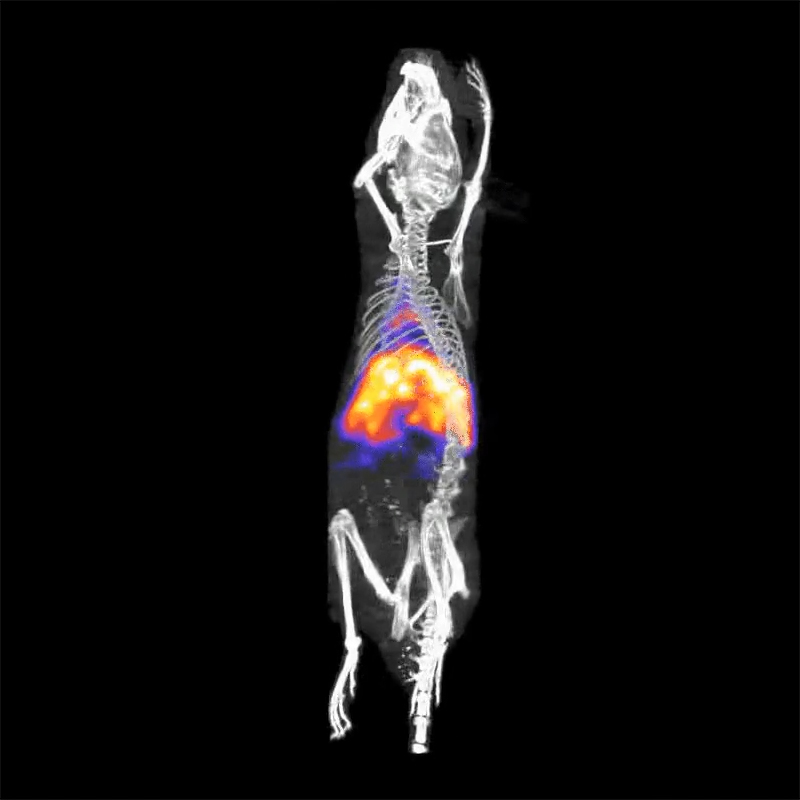

治疗性成像:使用131I对小鼠进行成像

专用的高能多孔准直器能够用于对131I这类治疗性示踪剂进行成像。

〉实验对象:18克重的小鼠

〉放射性示踪剂剂量:2.5 MBq(68 µCi)

〉示踪剂类型:131I-白蛋白结合物

〉准直器类型:用于小鼠全身成像的高能多孔准直器

〉采集方式:螺旋形SPECT扫描